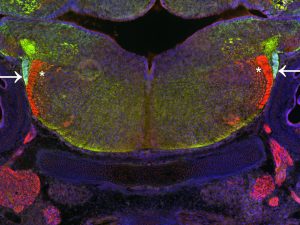

Mehr erfahren zu: "Epilepsie durch veränderte Abwehrmechanismen im Gehirn" Epilepsie durch veränderte Abwehrmechanismen im Gehirn Wissenschaftliche Studie bekräftigt die Bedeutung der Gliazellen bei epileptischen Anfällen und zeigt Potenziale für neue Therapien auf.